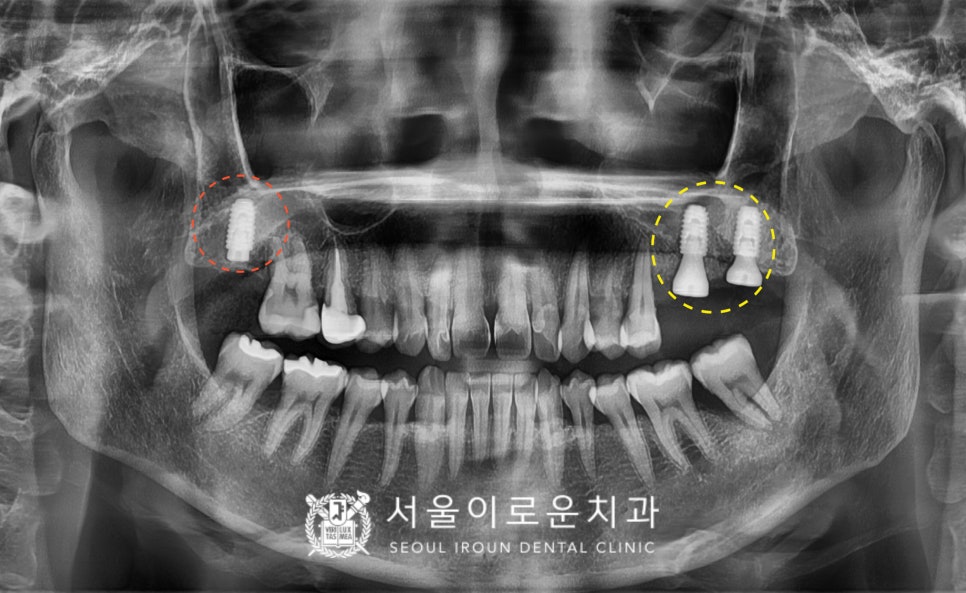

양측 임플란트 식립 후 3~4개월 뒤

osstell beacon이라는

골 유착을 확인할 수 있는

장비를 이용하여

isq 측정하여 뼈와 임플란트가

잘 결합한 것을 확인한 뒤

보철 과정을 진행하였는데요.

인상 채득시 환.자분께서

인상재로 인한 불편감을 느끼지 않아도 되고

인상 오차가 작고, 속도가 빠르며

보철물 제작시간을 단축시킬 수 있는

구강 스캐너를 이용하여

인상 채득을 도와드렸으며,

환.자분 구강 내 상황에 맞는

맞춤형 지대주인

custom abutment를 체결하여

자연치아와 강도가 가장 유사하고

심미적인 지르코니아 크라운으로

임플란트 보철을 마무리하였습니다.

그리고 위턱 첫 번째 큰 어금니(#16)는

충치를 제거한 뒤 확인해 보았더니

치아에 금이 관찰되어

처음 계획했던 인레이 진행이

어려울 것으로 판단되었는데요.

신경치료 + 크라운 수복으로

계획을 변경하였고,

뿌리 끝까지 깔끔하게

신경치료를 마무리한 뒤

크라운 수복까지 성공적으로 도와드렸답니다.

임플란트 / 신경치료 + 크라운수복

치료를 모두 마무리 한 모습입니다.

환.자분께서는 치료 전

치아가 흔들리고

씹.을때 아팠던 상태가 사라져

만.족해 하셨으며,

위턱 오른쪽 첫 번째 큰 어금니(#16)의 경우

씹.을때와 차가운 음식을 먹을 때

통증이 모두 사라졌다며 만.족해 하셨습니다.